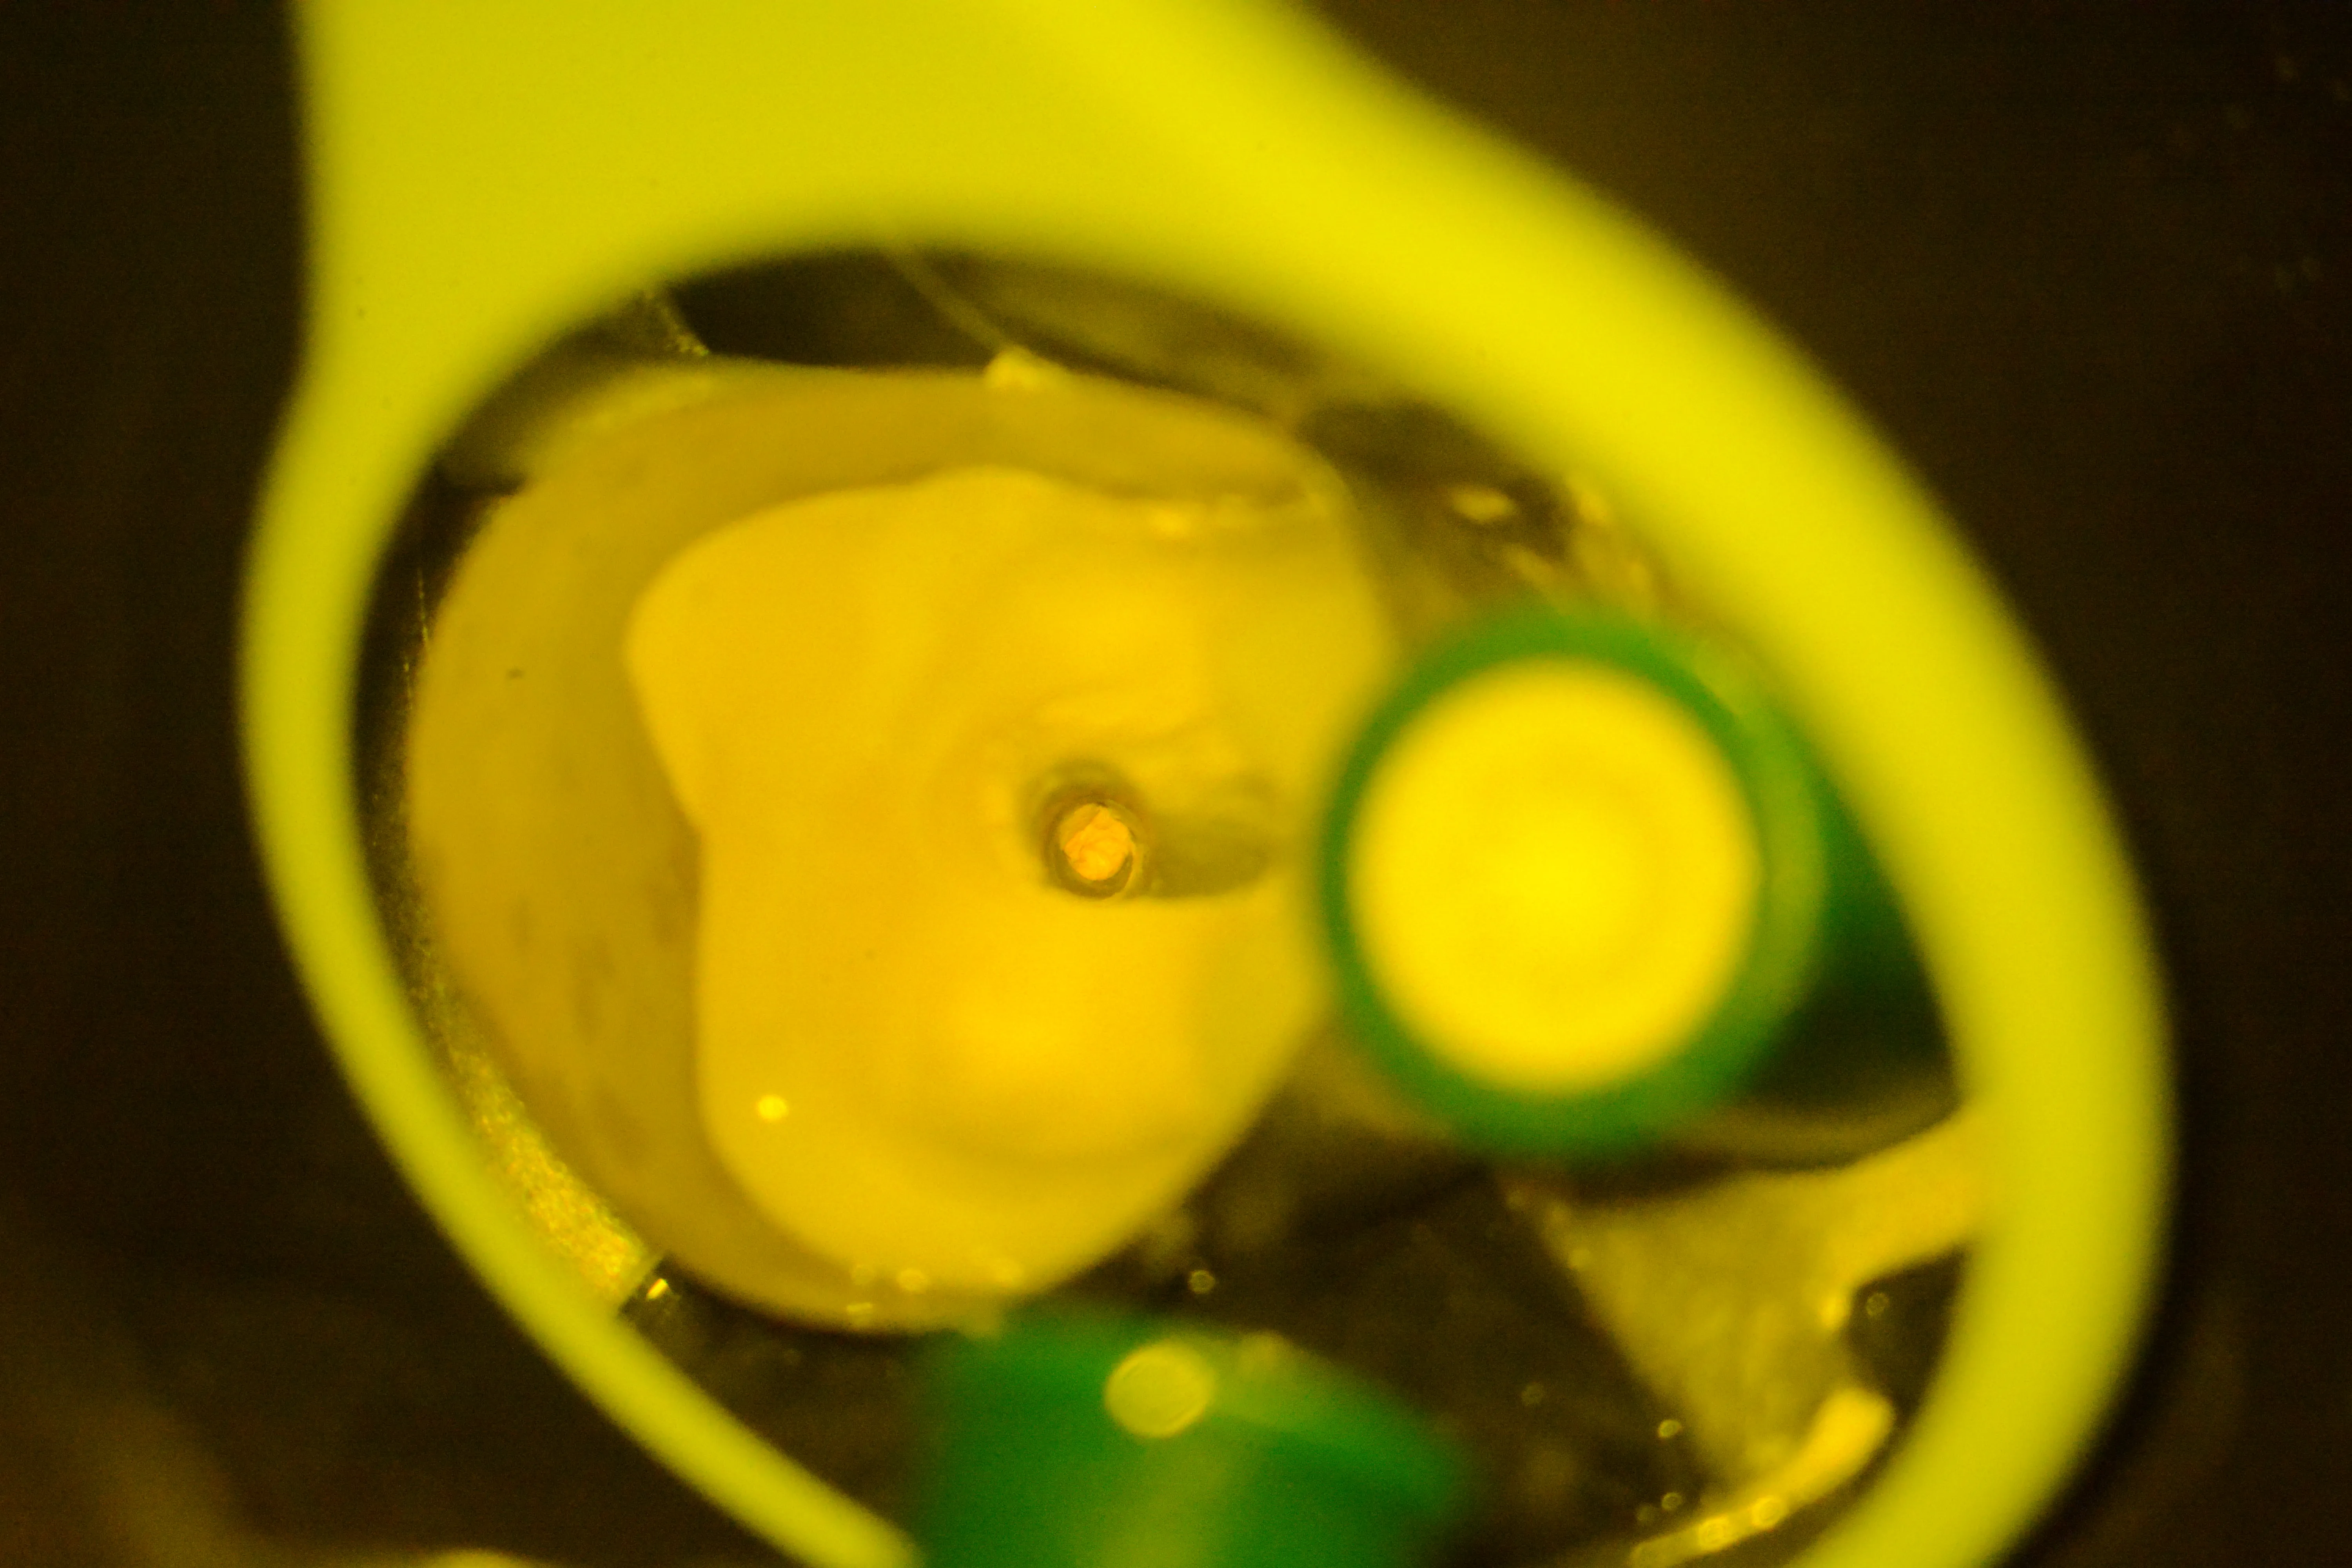

4 – Tratament mecanico-antiseptic